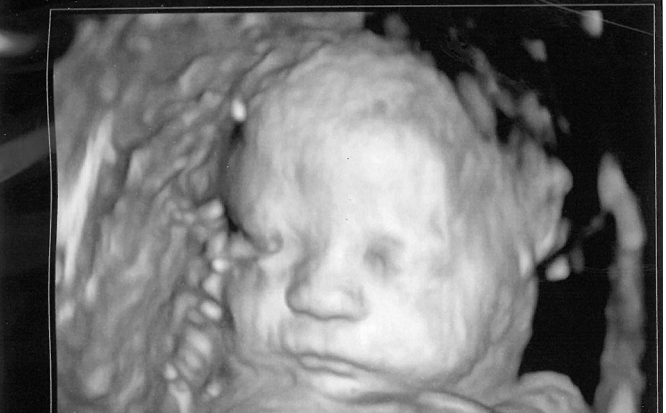

• Catholic Bishops Condemn Abortion: “Respect the Dignity of the Baby in the Womb”